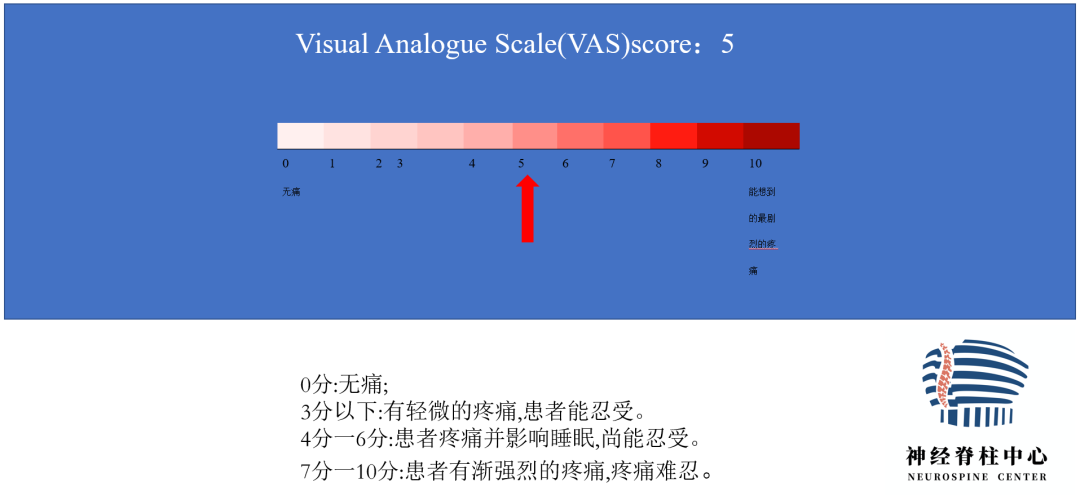

腰背痛2年,加重伴腰部后凸不能直立半年

Diagnosis:

腰椎侧后凸畸形

腰椎陈旧性压缩性骨折(L4)